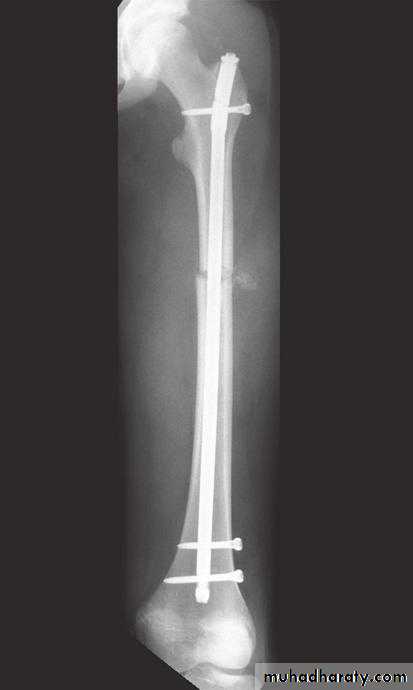

1-OSTEOTOMY:Osteotomy may be used to correct deformity, to change the shape of the bone, or to relieve pain in arthritis by redirecting the load.2-BONE FIXATION (internal or external fixation).

Internal and External fixation